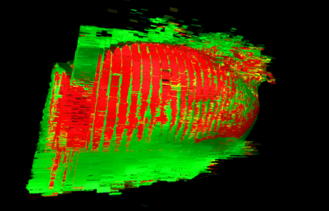

The quantification of fat depots on the surroundings of the heart is an accurate procedure for evaluating health risk factors correlated with several diseases. However, this type of evaluation is not widely employed in clinical practice due to the required human workload. This work proposes a novel technique for the automatic segmentation of cardiac fat pads. The technique is based on applying classification algorithms to the segmentation of cardiac CT images. Furthermore, we extensively evaluate the performance of several algorithms on this task and discuss which provided better predictive models. Experimental results have shown that the mean accuracy for the classification of epicardial and mediastinal fats has been 98.4% with a mean true positive rate of 96.2%. On average, the Dice similarity index, regarding the segmented patients and the ground truth, was equal to 96.8%. Therfore, our technique has achieved the most accurate results for the automatic segmentation of cardiac fats, to date.

翻译:心脏周围脂肪库的量化是评价与若干疾病相关的健康风险因素的准确程序。然而,由于需要人的工作量,这种评价在临床实践中没有被广泛采用。这项工作提出了心脏脂肪垫的自动分解新技术。该技术的基础是对心脏CT图像的分解应用分类算法。此外,我们广泛评价了这项任务的若干算法的性能,并讨论了这些算法提供了更好的预测模型。实验结果显示,震动和中间脂肪分类的平均准确性为98.4%,平均真实正率为96.2%。平均而言,关于分解病人和地面真相的骰子相似性指数为96.8%。我们的技术迄今为止在心脏脂肪的自动分解方面已经取得了最准确的结果。